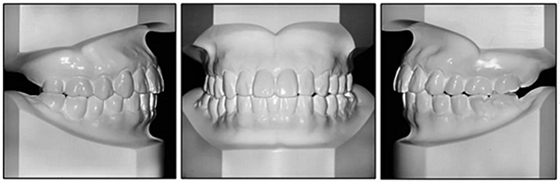

36歲;女性;尋求下頜左后方區(qū)域間隙管理的建議(圖1和圖2),通過治療獲得了良好的牙頜面效果(圖3和圖4)。她被診斷患有骨性I類和代償性牙性II類錯合畸形,并且上頜左側尖牙缺失(圖1和2)。大約七年前,由于不可修復的齲齒,拔除了下頜左側第一和第二磨牙(圖5)。37相鄰的第三磨牙向近中移動并傾斜入間隙,導致無牙頜間隙減小至約14 mm(圖2和圖5)。臨床和影像學評估顯示多發(fā)性齲損和在下頜右側567處有一不良的固定橋修復體(圖1和5)。此外,下頜左中切牙缺失,造成下頜中線向左側偏移約3 mm(圖1和圖2)?;颊咦栽V,她的右上第一前磨牙和左上尖牙在13歲時由其家庭牙醫(yī)拔除,因為它們被阻塞到頰側萌出(圖1)。上頜第二磨牙缺失(未知病因),并且相鄰的第三磨牙已經(jīng)轉移到第二磨牙間隙中。如補充材料所示,美國正畸學差異指數(shù)DI是28分。種植體部位(下頜左側和右側第一磨牙)由于復雜性得到額外4分(補充材料)。

圖1. 治療前面部和口內(nèi)照片